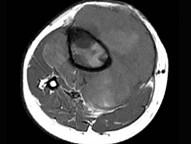

问题 男,35岁,胫骨中上段剧烈疼痛,尤以夜间明显,可摸到肿物,请结合图像,选择最佳选项 ( )

选项 A、骨肉瘤 B、骨巨细胞瘤 C、软骨肉瘤 D、骨转移瘤 E、软骨瘤

答案 A